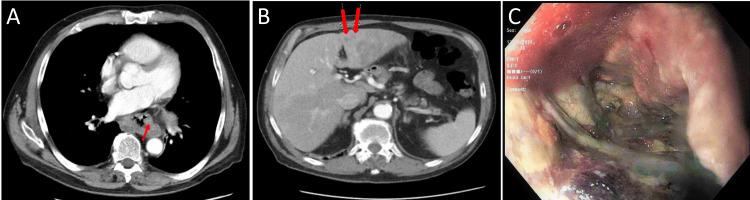

Undifferentiated esophageal carcinomas (UEC) are rare, with aggressive behavior and a dismal prognosis. An extremely rare subset is the SMARCA4-deficient UEC, which has only been reported in 14 cases to date. We present two cases of male patients (39- and 64-year-old) with SMARCA4-deficient UEC. Both patients had evidence of metastatic disease on presentation, progressed rapidly, and passed away within three months from the presentation. We aim to raise awareness of this underreported disease and contribute to the exploration of the possible underlying pathology and risk factors.

未分化食管癌(UEC)较为罕见,具有侵袭性且预后不佳。一种极其罕见的亚型是SMARCA4缺陷型UEC,迄今为止仅报道了14例。我们报告了两例男性患者(39岁和64岁)患有SMARCA4缺陷型UEC。两名患者就诊时均有转移疾病的证据,病情进展迅速,就诊后三个月内死亡。我们旨在提高对这种报道不足的疾病的认识,并为探索可能的潜在病理和危险因素做出贡献。